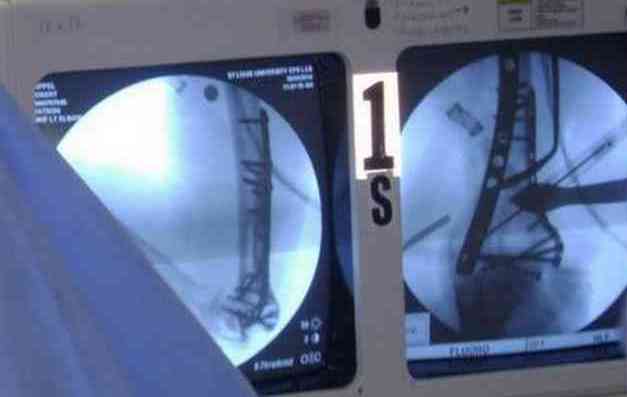

несколько примеров изящной работы ортопедов из СентЛуиса.В первом случае у

политравмированного пациента под ЭОП динамической пробой верифицирован разрыв МБС и

выполнена фиксация позиционными винтами, 3.5 кортикальными. Кстати метчика в работе мы не

видели, все винты self tapping. Во втором случае у пациента с открытым многооскольчатым

переломом дистального плеча на 4 сутки выполнен остеосинтез. Обратите внимание =доступ без

резекции олекранона,медленная и ювелирная работа нетипичным для нас инструментом

закончена полным восстановлением анатомии локтевого сустава. В небольшой дефект залит

БМП\OP-1 Stryker ,продукт роста клеток человека в генной модификации\. Для профилактики

гетеротопической оссификации ряд врачей применяют облучение на 2-3 сутки.